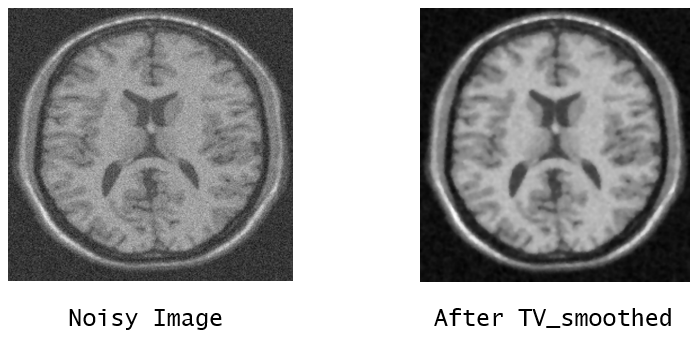

c. Total Variation - Total variation denoising (TVD) is a noise reduction technique designed to keep the underlying signal’s sharp edges. A functional consisting of the sum of fidelity and regularisation components is minimised via TV regularisation.

Refer to caption

Figure 6: Kernel SVM

The best result which is obtained by BM3D denoising is used for further process.